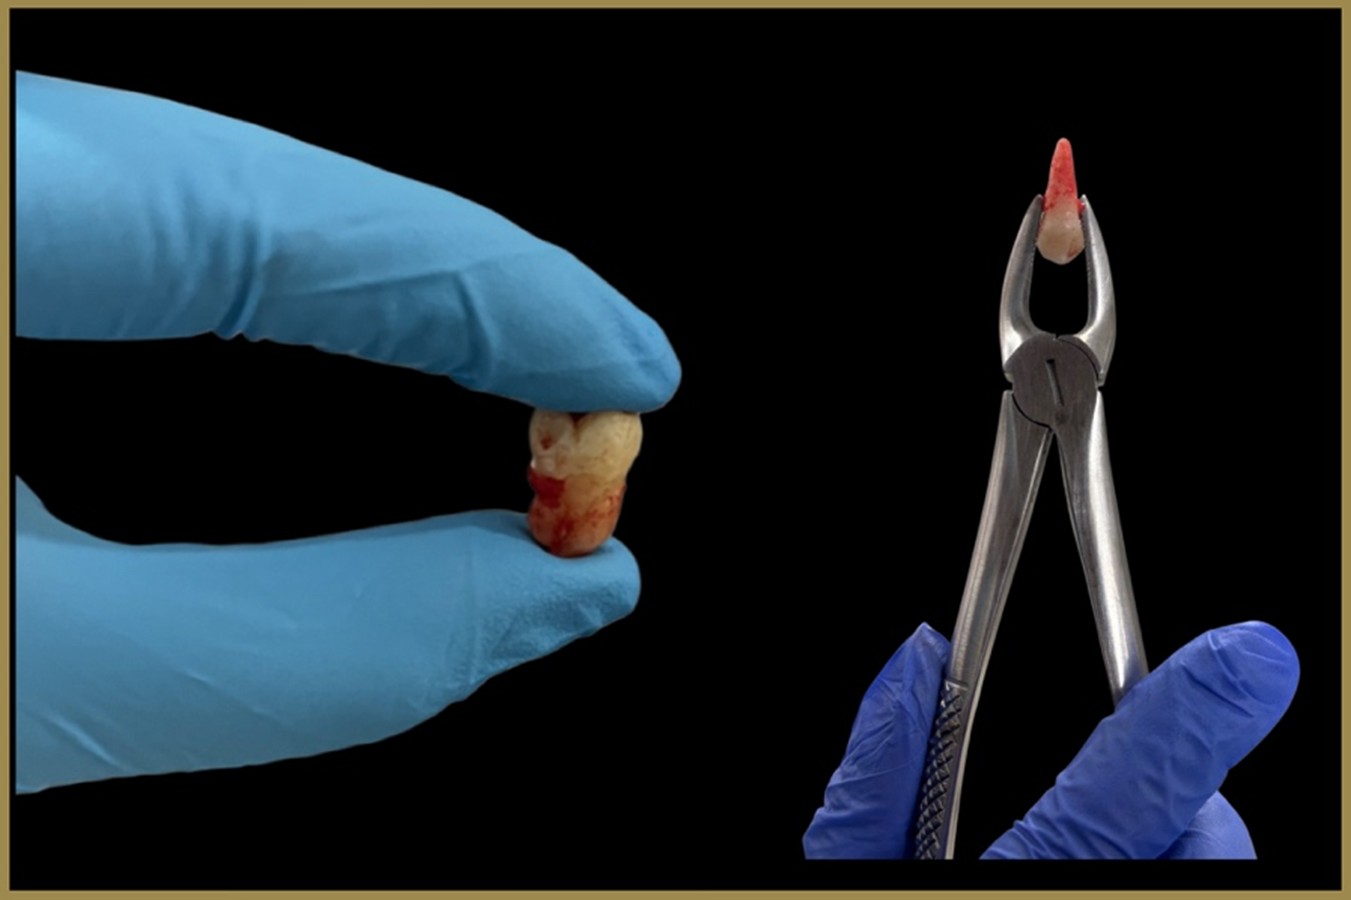

While our primary goal is always to save natural teeth, sometimes an extraction becomes necessary to protect overall oral health. At Elite Dental Care and Aesthetics, we perform both simple and surgical extractions with utmost care, ensuring comfort, safety, and minimal recovery time.

A simple extraction is usually performed when the tooth is visible and can be easily removed. A surgical extraction is needed when a tooth is impacted, broken, or not easily accessible, such as in the case of wisdom teeth. Our experienced dentists use advanced techniques and gentle approaches to make the procedure as stress-free and painless as possible.

When is an extraction needed?

Severe tooth decay or damage beyond repair

Impacted or infected wisdom teeth

Advanced gum disease causing tooth mobility

Overcrowding before orthodontic treatment

Broken teeth that cannot be restored

How do we ensure comfort?

Detailed Examination – X-rays and evaluation to plan the safest approach

Local Anesthesia – Ensures the procedure is pain-free

Gentle Techniques – Minimally invasive methods to reduce trauma

Post-Operative Care – Clear instructions and follow-up to aid fast healing

Benefits of Professional Extractions

Relieves Pain – Removes the source of discomfort or infection

Prevents Spread of Infection – Protects nearby teeth and gums

Improves Oral Health – Creates a healthier foundation for restorations or orthodontics

Safe & Precise – Performed with modern tools and sterilization standards

Faster Recovery – With expert care and guided aftercare

At Elite Dental Care, we understand that extractions may cause anxiety, which is why we prioritize patient comfort, compassionate communication, and advanced pain management techniques. Whether it’s a simple tooth removal or a complex surgical extraction, your safety and well-being are always our top priority.